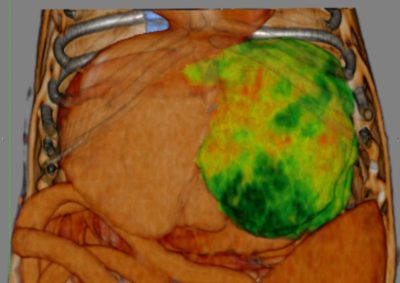

腫瘍外科 注意 ボタンをクリックした先に、治療中および手術中の画像が説明で使用されている場合がございます。 そのような画像に弱い方は閲覧なさらないようお願いいたします。 腫瘍外科 フレンチブルドッグ胃腺癌 胃部分切除 軟部組織外科腫瘍外科救急・集… 肝臓腫瘤破裂による腹腔内出血 腫瘍外科腫瘍内科 猫の直腸切除吻合 直腸リンパ腫 腫瘍外科 犬の肺腺癌の1例 腫瘍外科放射線治療 犬の軟部組織肉腫に対する腫瘍辺縁切除及び術後放射線療法 腫瘍外科 犬の肝細胞癌 軟部組織外科腫瘍外科 ジャックラッセルテリアの胃腫瘍 腫瘍外科 吻側下顎骨切除術〜メラノーマ〜 腫瘍外科 猫の上顎腫瘍切除 腫瘍外科 犬の脾臓腫瘤摘出 軟部組織外科腫瘍外科 大腸腺癌 軟部組織外科腫瘍外科 肺葉切除術 <1234567> 症例カテゴリー 放射線治療整形外科軟部組織外科脳神経外科内科腫瘍外科救急・集中治療リハビリテーション科腫瘍内科内視鏡科脳神経科呼吸器外科中医・漢方猫の腎移植循環器科